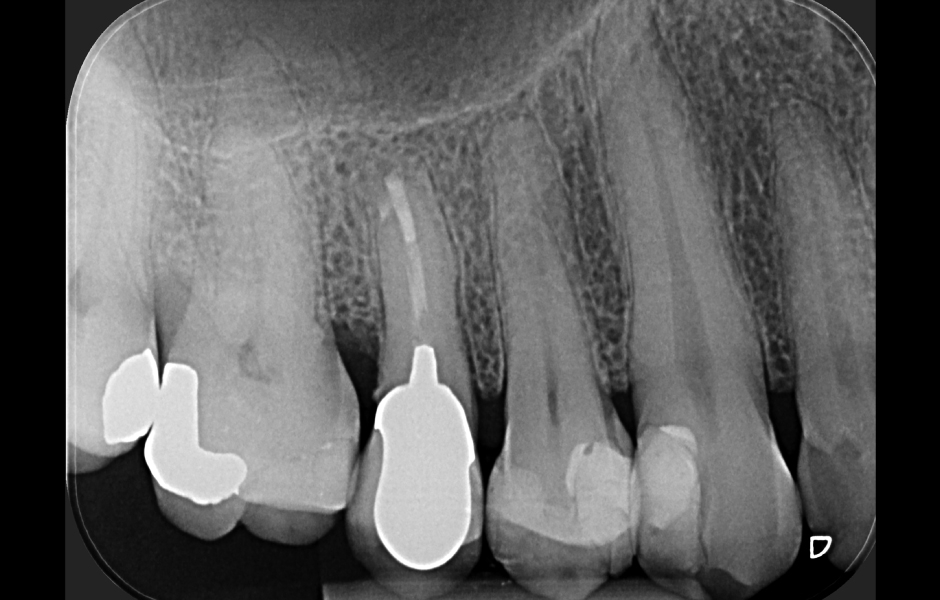

Obr. 4.1: Předoperační snímek horního levého prvního moláru. Oba kanálky mesiobukálního kořene byly kompletně kalcifikované a nebylo možné je ortográdně zprůchodnit.

Obr. 4.4: Pooperační rentgenový snímek zobrazující retrográdní výplň z bílého MTA.

Obr. 4.6: Kontrola po třech letech se zhojením léze.